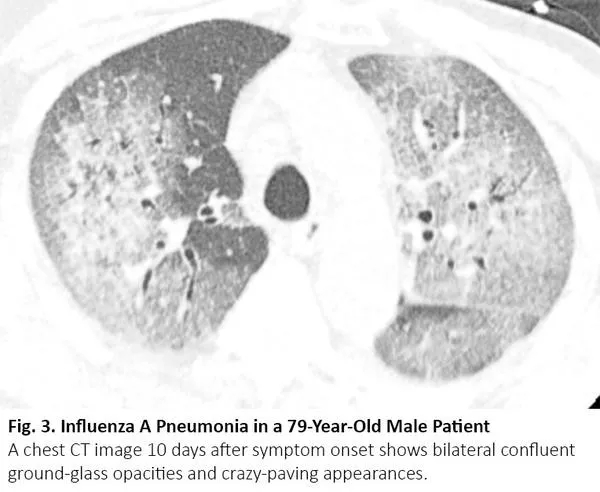

放疗结束后4~12周内可能发生放射性肺炎,有时更晚15。因为放射性肺炎通常发生在照射野,发生于局部,因此在大多数情况下,放射性肺炎与COVID-19肺炎的影像鉴别很简单。然而,当肺炎呈弥漫性分布时,可能无法将放射性肺炎与COVID-19肺炎区分(图5)。

图5. 一位77岁肺腺癌女性患者出现放射性肺炎